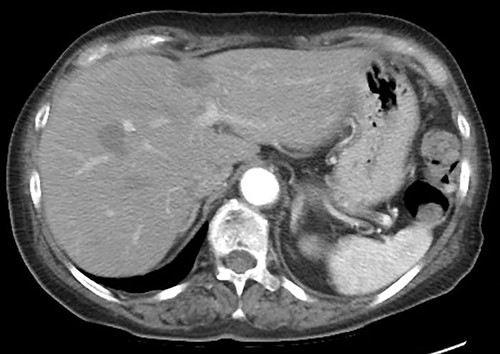

A 75-year-old bedridden woman presented to our hospital with chief complaints of epigastric pain, anorexia and a palpable mass in the epigastric region. She had a history of surgery for meningioma, but no history of abdominal surgery. Ultrasonography revealed a well-defined large cystic lesion with a long diameter of approximately 150 mm in the left liver lobe. Contrast-enhanced computed tomography showed a giant hepatic cyst with an irregular mass in liver segment 4, 20 × 16 cm in size (Fig. 1).

The hepatic cyst compressed the stomach, duodenum, pancreas and gallbladder, and the descending part of the duodenum was difficult to identify because of severe thinning caused by the compression. On magnetic resonance imaging, the giant cyst showed low signal intensity on T1-weighted and high signal intensity on T2-weighted images, and there was a solid component with a high signal on diffusion-weighted images on the dorsal side of the cyst (Fig. 2).

The postoperative course was uneventful, and the patient was discharged on the eighth postoperative day. Follow-up computed tomography at 3 months postoperatively showed no recurrence of the liver cyst (Fig. 7).